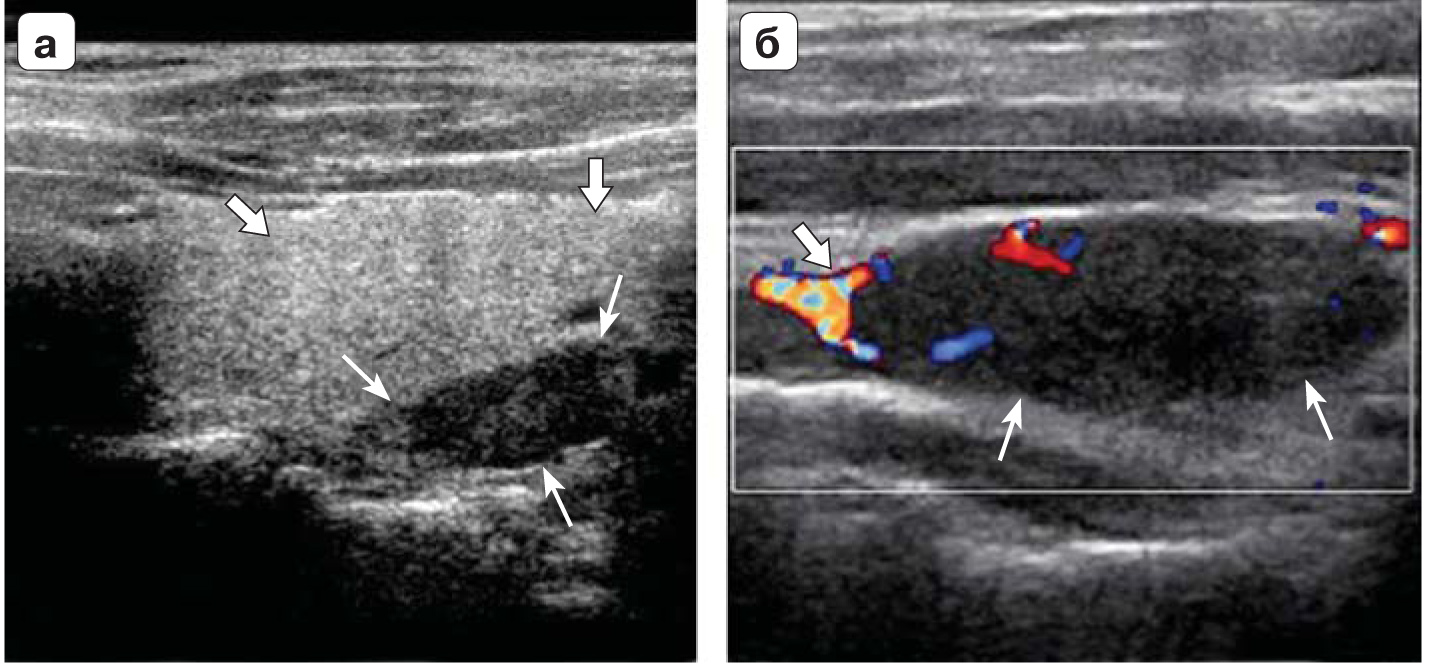

3. Fig. 2. a - ultrasound, with a longitudinally located sensor hypoechoic formation (thin arrow) behind the left lobe of the thyroid gland (thick arrow); b - in the color Doppler mode, hypoechoic formation of the thyroid gland (thin arrow) with typically enhanced vascularization at one of the poles (thick arrow) (images from Diagnostic Imaging: head and neck, 3rd edition, Elsevier 2017). | |

| Subject | ||

| Type | Other | |

View

(316KB)

|

Indexing metadata ▾ | |